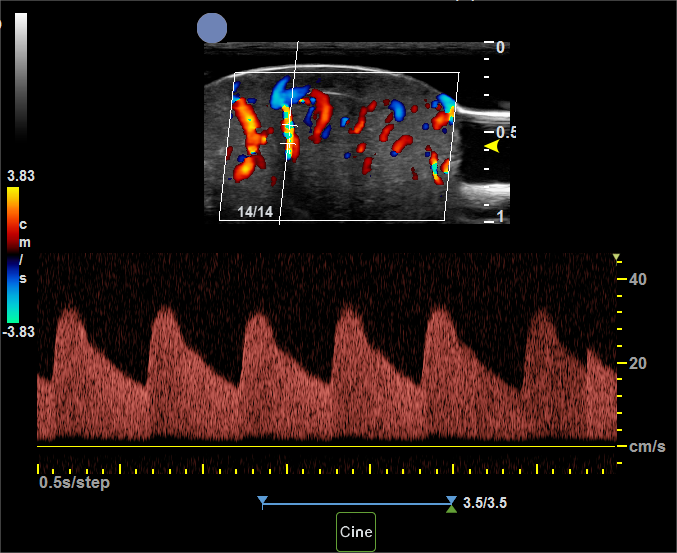

基于全球领先的CMUT半导体超声技术,集成近60项发明专利,珂纳医疗历经数年潜心研制,推出了Paragon XHD便携式彩色多普勒超声系统。该系统显微镜级的成像分辨率,为临床医生观察诊断表皮、真皮、皮下组织及皮肤附件提供了清晰的二维图像。丰富灵敏的彩色多普勒血流成像,满足了对于皮下血流,皮肤肿瘤状态的判定。方便实时的无创操作深受医生和患者青睐,为术前切缘深度测量,术后疗效评估以及医美玻尿酸注射引导等提供了极具价值的诊断信息。